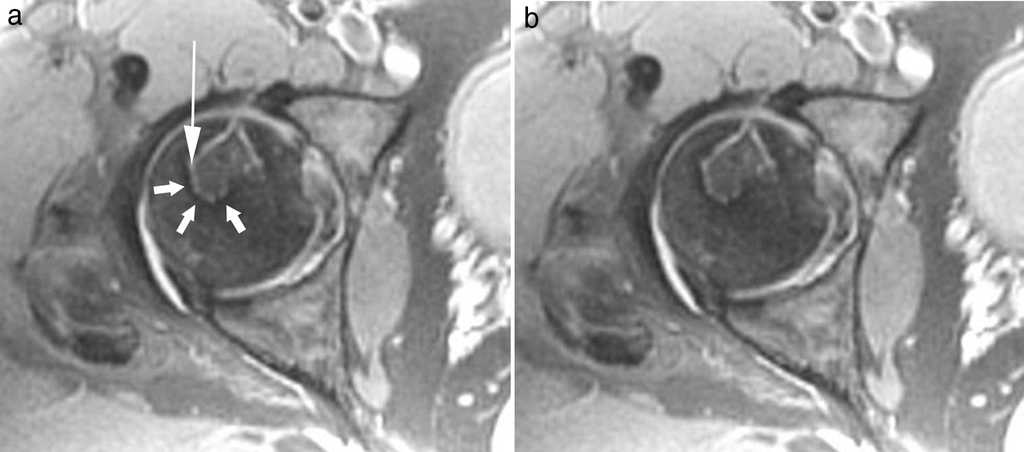

Este signo se observa, mediante la resonancia magn??tica (RM) con tiempo de repetici??n largo, como dos im??genes lineales adyacentes entre s??, de trazo serpiginoso, delimitando la interfase entre el hueso necr??tico y el normal: una banda hipointensa externa define el hueso normal y corresponde a tejido fibr??tico y esclerosis, mientras que la otra banda, hiperintensa, tiene una localizaci??n interna, delimita el hueso necr??tico y representa tejido de granulaci??n hipervascular de reparaci??n de la zona de necrosis2,3 (figs. 1 y 2).

El signo de la doble l??nea es importante en el diagn??stico de la necrosis avascular. A pesar de que existen otros signos descritos por radiolog??a simple, tomograf??a computada y RM, este es el de mayor especificidad. Una vez diagnosticado el proceso, dado que el signo permite diferenciar claramente el hueso necr??tico del normal, resulta esencial en la clasificaci??n, planificaci??n terap??utica y seguimiento. Su presencia permite valorar la localizaci??n, extensi??n, morfolog??a y volumen del hueso necr??tico, susceptible de tratamiento y control.

Adem??s, al ser un hallazgo relativamente precoz (ya hay reparaci??n ??sea), su existencia, junto con otros patrones de representaci??n en RM, posibilita el diagn??stico en pacientes con sospecha cl??nica, pero con otras pruebas de imagen sin alteraciones significativas (estadio I)3.